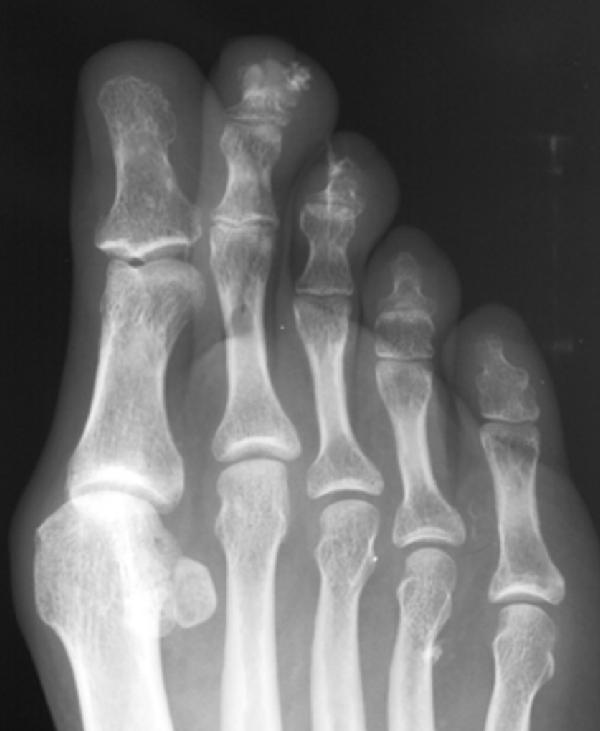

Инструментальные обследования при дерматомиозите